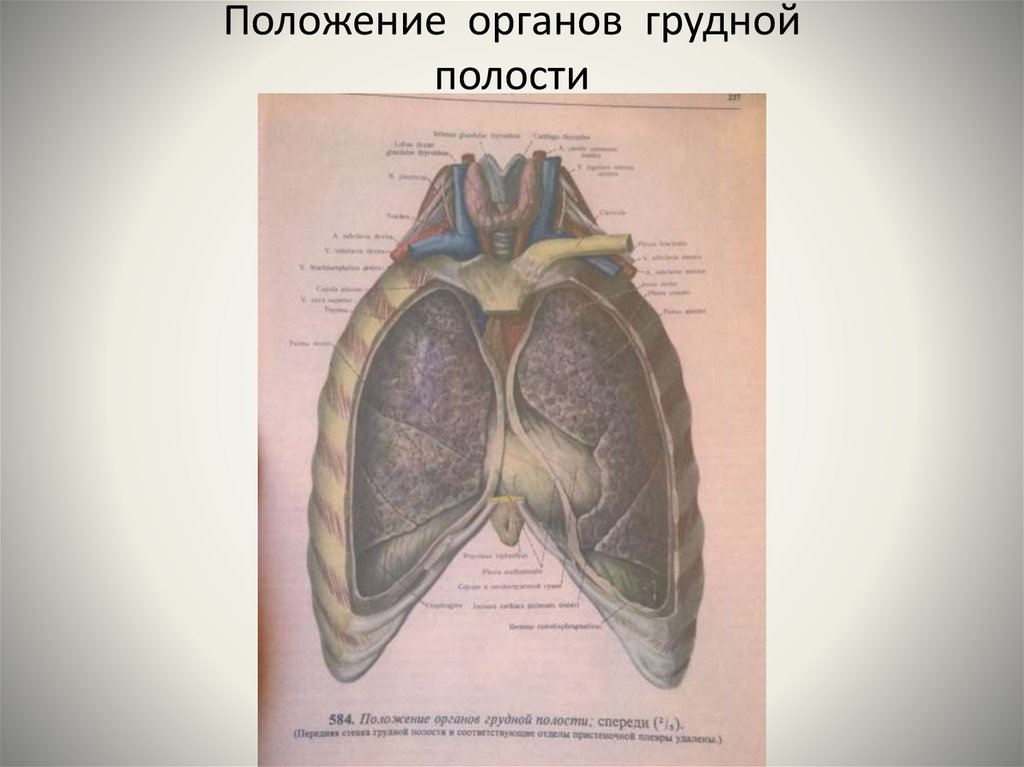

Анатомия Сердца: Расположение и Функции